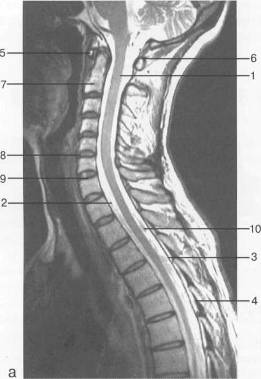

Рис. 12. МРТ. Срединное

сагиттальное изображение шейного отдела позвоночника. а-Т2-ВИ;б-Т1-ВИ.

- спинной мозг; 2 -

субарахноидальное пространство; 3 - дуральный мешок (задняя стенка); 4 -

эпидуральное пространство; 5 - передняя дуга С1; 6 - задняя дуга С1; 7 - тело

С2; 8 - межпозвонковый диск; 9 - гиалиновая пластинка; 10 - артефакт

изображения; 11 - остистые отростки позвонков; 12 - трахея; 13 - пищевод.